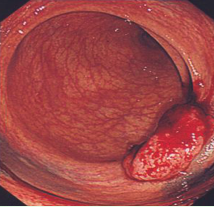

大腸がんは下のような大腸造影検査(注腸検査)、大腸カメラ(大腸内視鏡検査)にて発見、確認することができます。病変の場所、進行の程度により、腸を切る場所や範囲が変わってきます。

S状結腸という場所にできた大腸がんです。がんのために、腸が狭くなっています

肛門から約5cmの位置に出来た大腸がん(直腸癌)です。このような肛門に近いがんも、条件がそろえば人工肛門は作らずに腹腔鏡下に手術することが可能です。